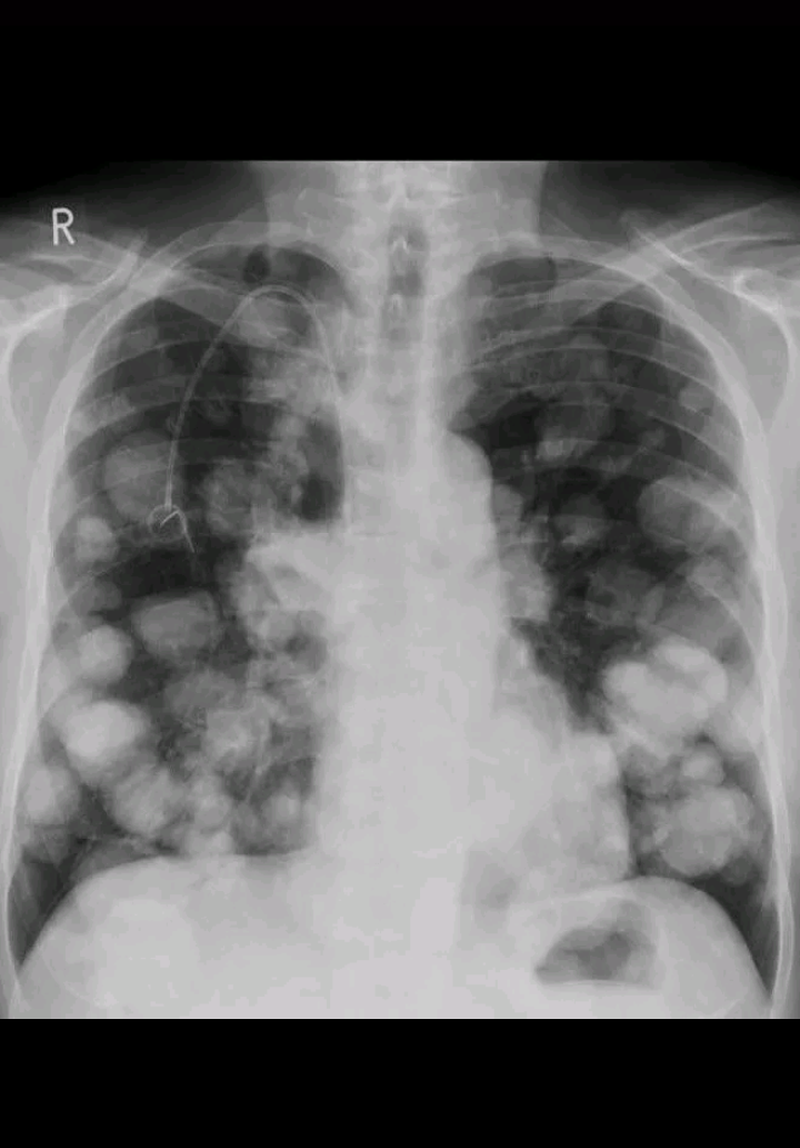

Cannon ball - metastasis

Emphysema due to bullous formation in the left lung